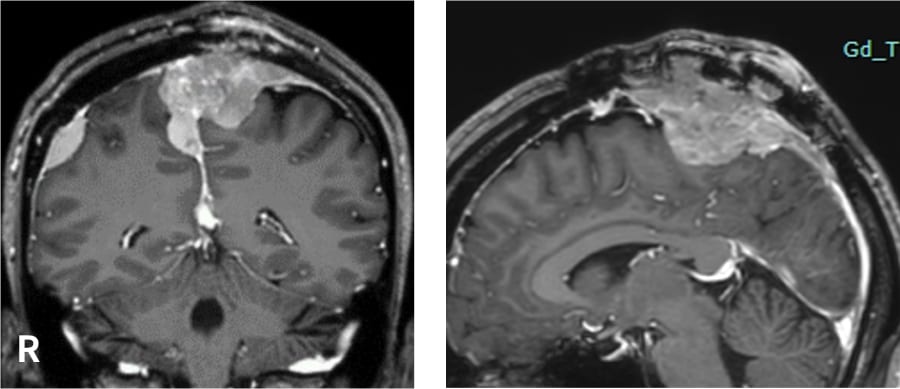

上矢状静脈洞を充満する異型髄膜腫。傍矢状洞に加え、大脳鎌、右円蓋部などに多発する腫瘍がみられる。

上矢状洞を切断する手術では脳の静脈の流れに大きな影響を生じる可能性があり、手術の可否、タイミングが慎重に検討された。

開頭手術にて全摘出され、上矢状静脈洞切断断端には定位的放射線治療が施行された。

術前

術後

(手術後、上矢状静脈洞断端に定位的放射線治療後)